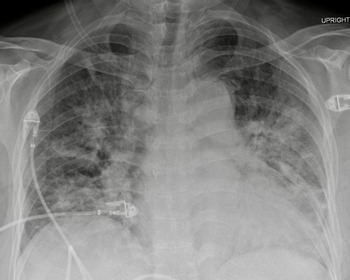

A 51-year-old woman presented with a 6-month history of left eye progressive central visual blurring that improved with lateral gaze. Her past medical history was significant for poorly controlled essential hypertension. Computer tomography angiogram of the head revealed a 5.2 × 5.2 cm supraclinoid internal carotid artery aneurysm. She underwent successful urgent endovascular occlusion of the left internal carotid artery proximal to the aneurysm. She was discharged home 5 days postoperatively on a dexamethasone taper and aspirin. Two months after discharge, she presented to the emergency department (ED) with a 1-week history of confusion and malaise 3 days after stopping dexamethasone. In the ED, she developed rapidly progressive hypoxemia and required endotracheal intubation and ventilation in the intensive care unit (ICU). Chest X-ray (CXR) demonstrated diffuse bilateral patchy infiltrates (Figure 1). In the ICU, bronchoalveolar lavage (BAL) was positive for PJP. Fortunately, she improved quickly on ventilatory support, TMP/SMX, and prednisone. She was extubated and discharged home.

Figure 1: AP chest radiograph demonstrating diffuse, bilateral, patchy, and confluent infiltrates with a predominant perihilar distribution.